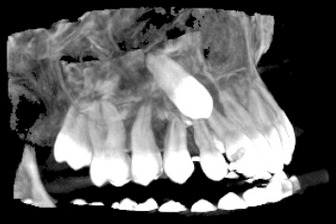

Зъбните снимки, независимо дали са секторни, панорамни зъбни снимки, телерентгенографии или друг вид се съхраняват на нашите сървъри неограничено дълго време.

Зъбните снимки са налични в няколко различни файлови формата - DICOM (DCM), PNG и JPG, което улеснява свалянето им на личните компютри.

Денталните медици могат с лекота да правят всички необходими обработки и измервания на дигиталните зъбни снимки, което улеснява подготовката за лечебния процес на пациента.